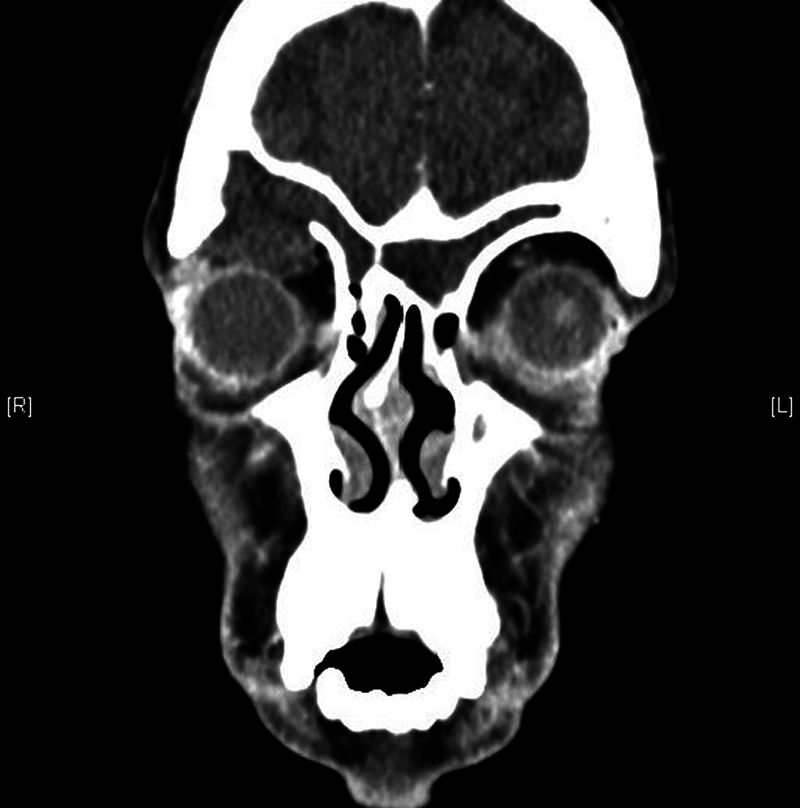

Introduction  Mucoceles are benign expansile cystic lesions commonly seen in the frontoethmoidal region. Objective  To see if the distribution of frontal air cells predisposes to mucocele formation. Methods  Retrospective review of all cases of paranasal sinus mucocele from 2011 to 2021. Data on demographics, history of surgery or trauma, clinical features, radiological findings, and outcome were collected and analyzed. Results  Of the 28 cases, 19 (67.9%) were male and 9 (32.1%), female, with a mean age of 40.75 years. Mucocele was unilateral in 26 (92.9%) patients. Twenty patients (71.43%) presented with primary mucocele. The distribution of mucocele was frontal and frontoethmoidal in 8 (28.6%) patients each, maxillary in 6 (21.4%), and ethmoid and sphenoid sinus in 3 (10.7%) patients each. Sixteen (57.1%) patients had frontal sinus involvement. At presentation, 13 (46.4%) patients had nasal symptoms, 17 (60.7%) had orbital symptoms, while 16 (57.1%) had headache. Pain (12; 70.59%) was the predominant orbital symptom, followed by proptosis and diplopia (8; 47.06%). The most common sites of bony erosions were along the frontal sinus floor (14; 50%), followed by lamina papyracea (13; 46.43%), and frontal sinus anterior wall (10; 35.71%). The agger nasi and suprabullar cells were the most common frontal cells encountered in mucoceles involving the frontal sinus, with no significant difference in frontal cell distribution between involved and uninvolved sides. The frontal cell distribution was similar in mucoceles with and without frontal sinus involvement too. Conclusion  Though frontal and frontoethmoidal mucoceles were the most encountered, the type and distribution of frontal cells did not predispose to mucocele formation.